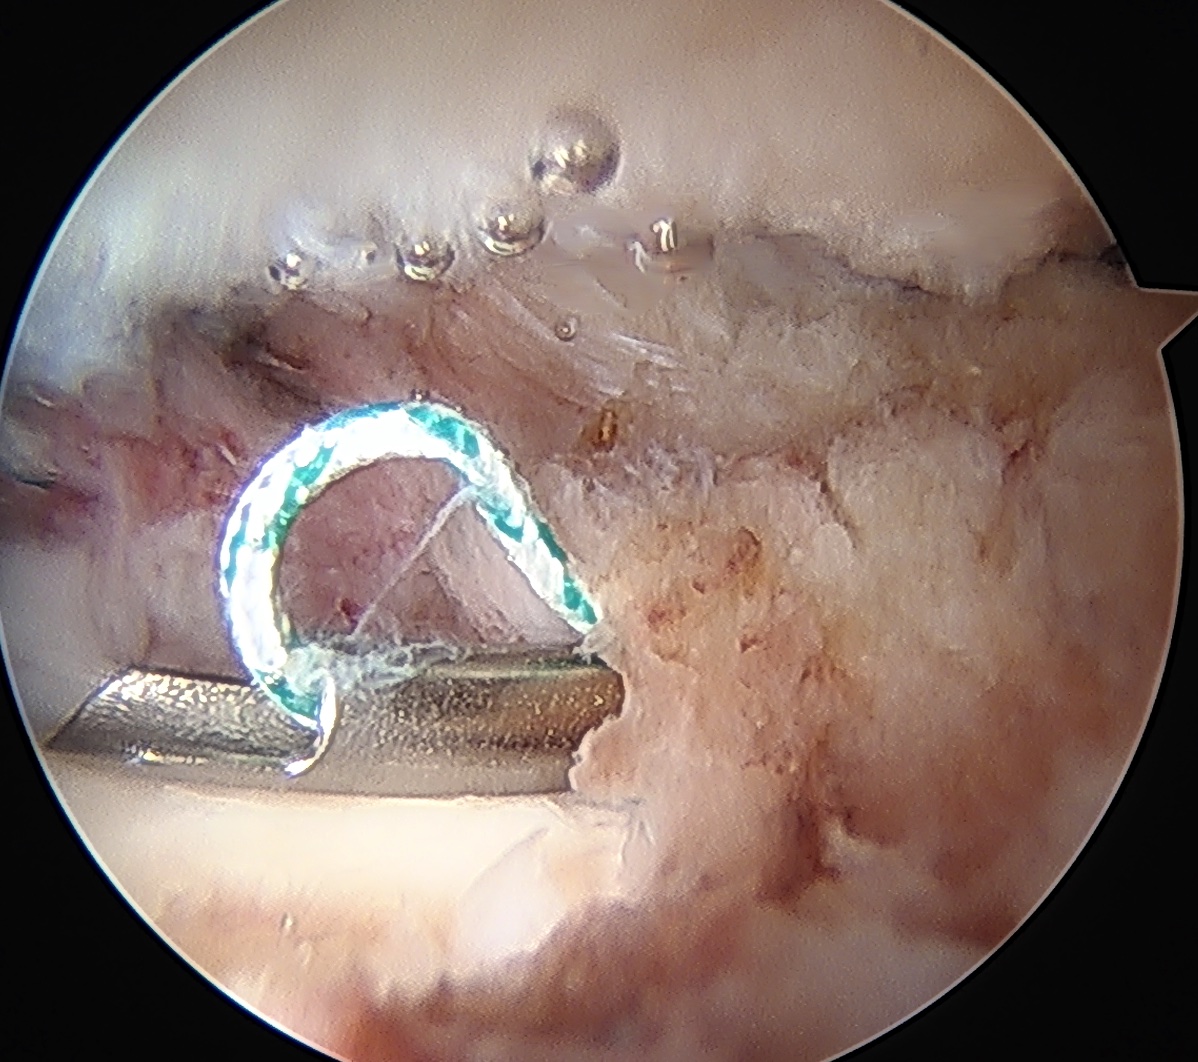

Labral repair

Options

- knotted versus knotless anchors

- straight versus curved

Must avoid intra-articular penetration